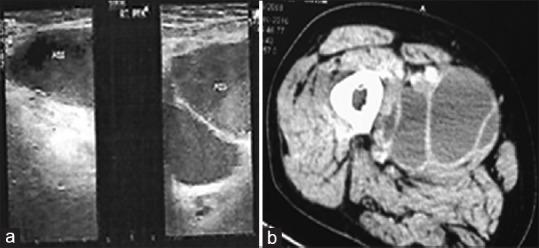

A 65-year-old male patient, a known case of carcinoma bladder, underwent radical cystectomy with ileal neobladder in 2016. Eleven lymph nodes were identified in the specimen. Histopathology revealed reactive lymphadenitis with sinus histiocytosis. The patient presented with a swelling in the right thigh, associated with dull pain, about 6 months after the procedure. Ultrasound of the right thigh and computed tomography of the region showed an isolated, large, loculated, cystic collection measuring 15 cm × 6 cm with internal septation in the pectineus and adductor longus muscles. Complete aspiration of fluid from the right thigh was done with ultrasound guidance and sent for analysis. The fluid appeared to be lymph, and the lesion turned out to be a lymphocele. There was no recurrence or infection following the aspiration till last follow-up visit. We report this rare lymphocele presentation (in the thigh without any extension from pelvis or groin) after 6 months, following radical cystectomy with neobladder, which was treated by one-time aspiration.

一名65岁男性患者,已知患有膀胱癌,于2016年接受了根治性膀胱切除术并采用回肠新膀胱术。标本中发现了11个淋巴结。组织病理学显示为伴有窦组织细胞增生的反应性淋巴结炎。该患者在手术后约6个月出现右大腿肿胀,并伴有钝痛。右大腿超声及该区域的计算机断层扫描显示在耻骨肌和长收肌中有一个孤立的、大的、有分隔的囊性肿物,大小为15 cm×6 cm。在超声引导下对右大腿的液体进行了完全抽吸并送去分析。液体似乎是淋巴液,结果发现该病变是一个淋巴管囊肿。直到最后一次随访,抽吸后均未出现复发或感染。我们报告了这例罕见的在新膀胱根治性膀胱切除术后6个月出现的淋巴管囊肿(位于大腿,没有从骨盆或腹股沟延伸而来),通过一次性抽吸进行了治疗。